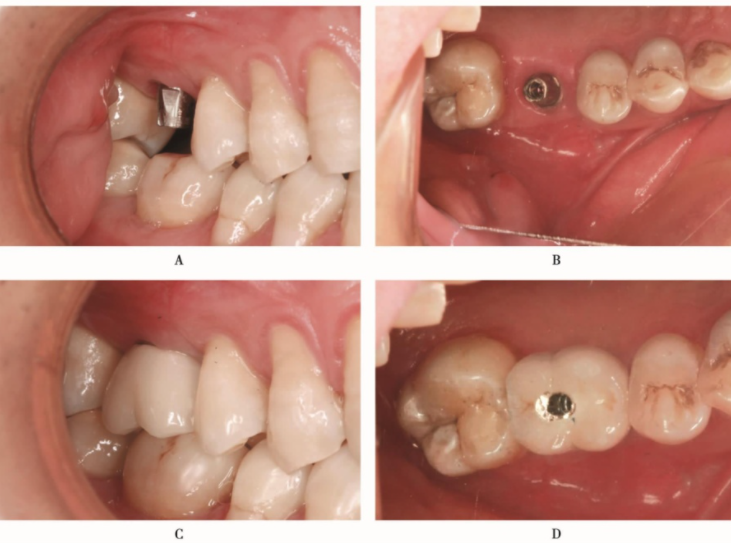

种植体植入后3个月,种植体周围骨结构良好,可以进行上部结构修复(图28)。完成上部结构修复(图29)

图28 种植体植入后3个月CBCTA.矢状位;B.冠状位;C.水平位

图29 完成上部冠修复A.颊面观;B.𬌗面观